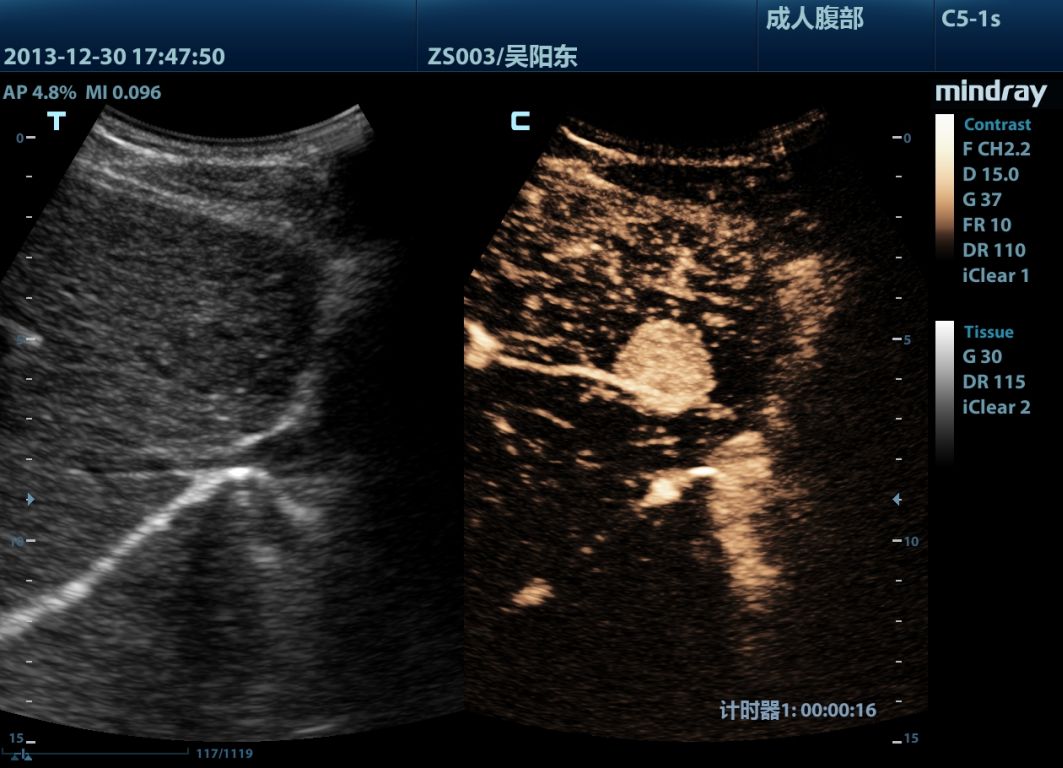

Mindray M9 je dopplerovský ultra ľahký prenosný UZV prístroj najvyššej High End triedy s použitím single crystal 3T sond (vynikajúce zobrazenie blízkeho i vzdialeného poľa), HDR FLOW, ECHO BOOST, Natural Touch Elastography, kontrastného zobrazenia, TDI. Špeciál hlavne pre kardiológiu.

Klinické obrázky: